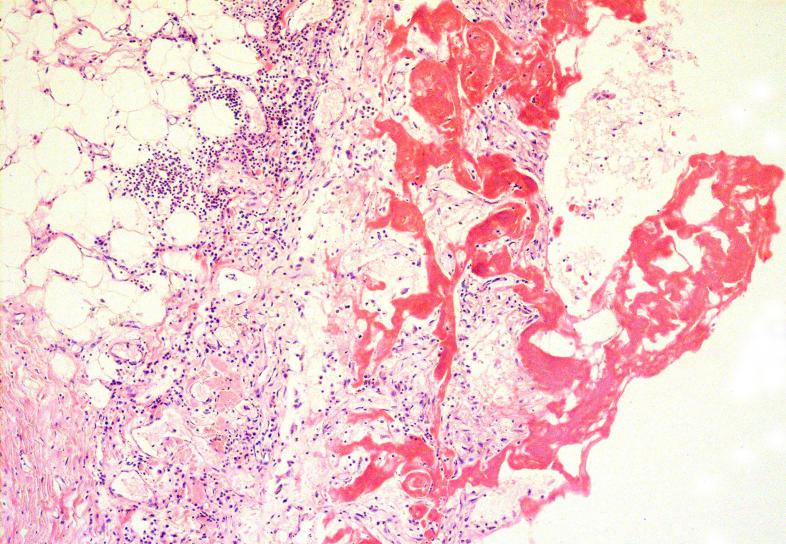

Межуточный миокардит: гистологические исследования

Раздел: Идеи и советы